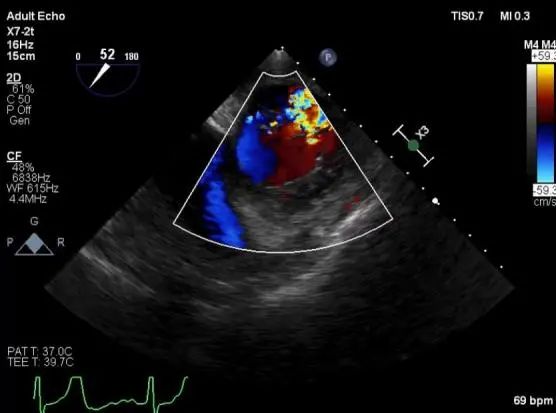

麻醉状态下TEE显示中大量返流MR:

患者麻醉方式采取全麻,建立静脉通路后,穿刺右侧股动脉以及股静脉,预埋ProGlide缝合器,冠脉造影复查提示支架通常。TEE超声指导下经房间隔穿刺后进入左房,送入鞘管,MitraClip调整后顺利到达二尖瓣目标位置,后在X线及食道超声辅助下,使用1枚XTR二尖瓣夹准确夹合二尖瓣A2-P2区,超声即刻测反流面积明显减少,LVOT切面,四腔心切面以及3D下证实夹合组织充分,患者收缩压由术前的108/62mmHg上升至130/72mmHg,左心房压力显著减低,肺静脉多普勒波形由反向恢复正常。手术顺利结束,安返普通病房。